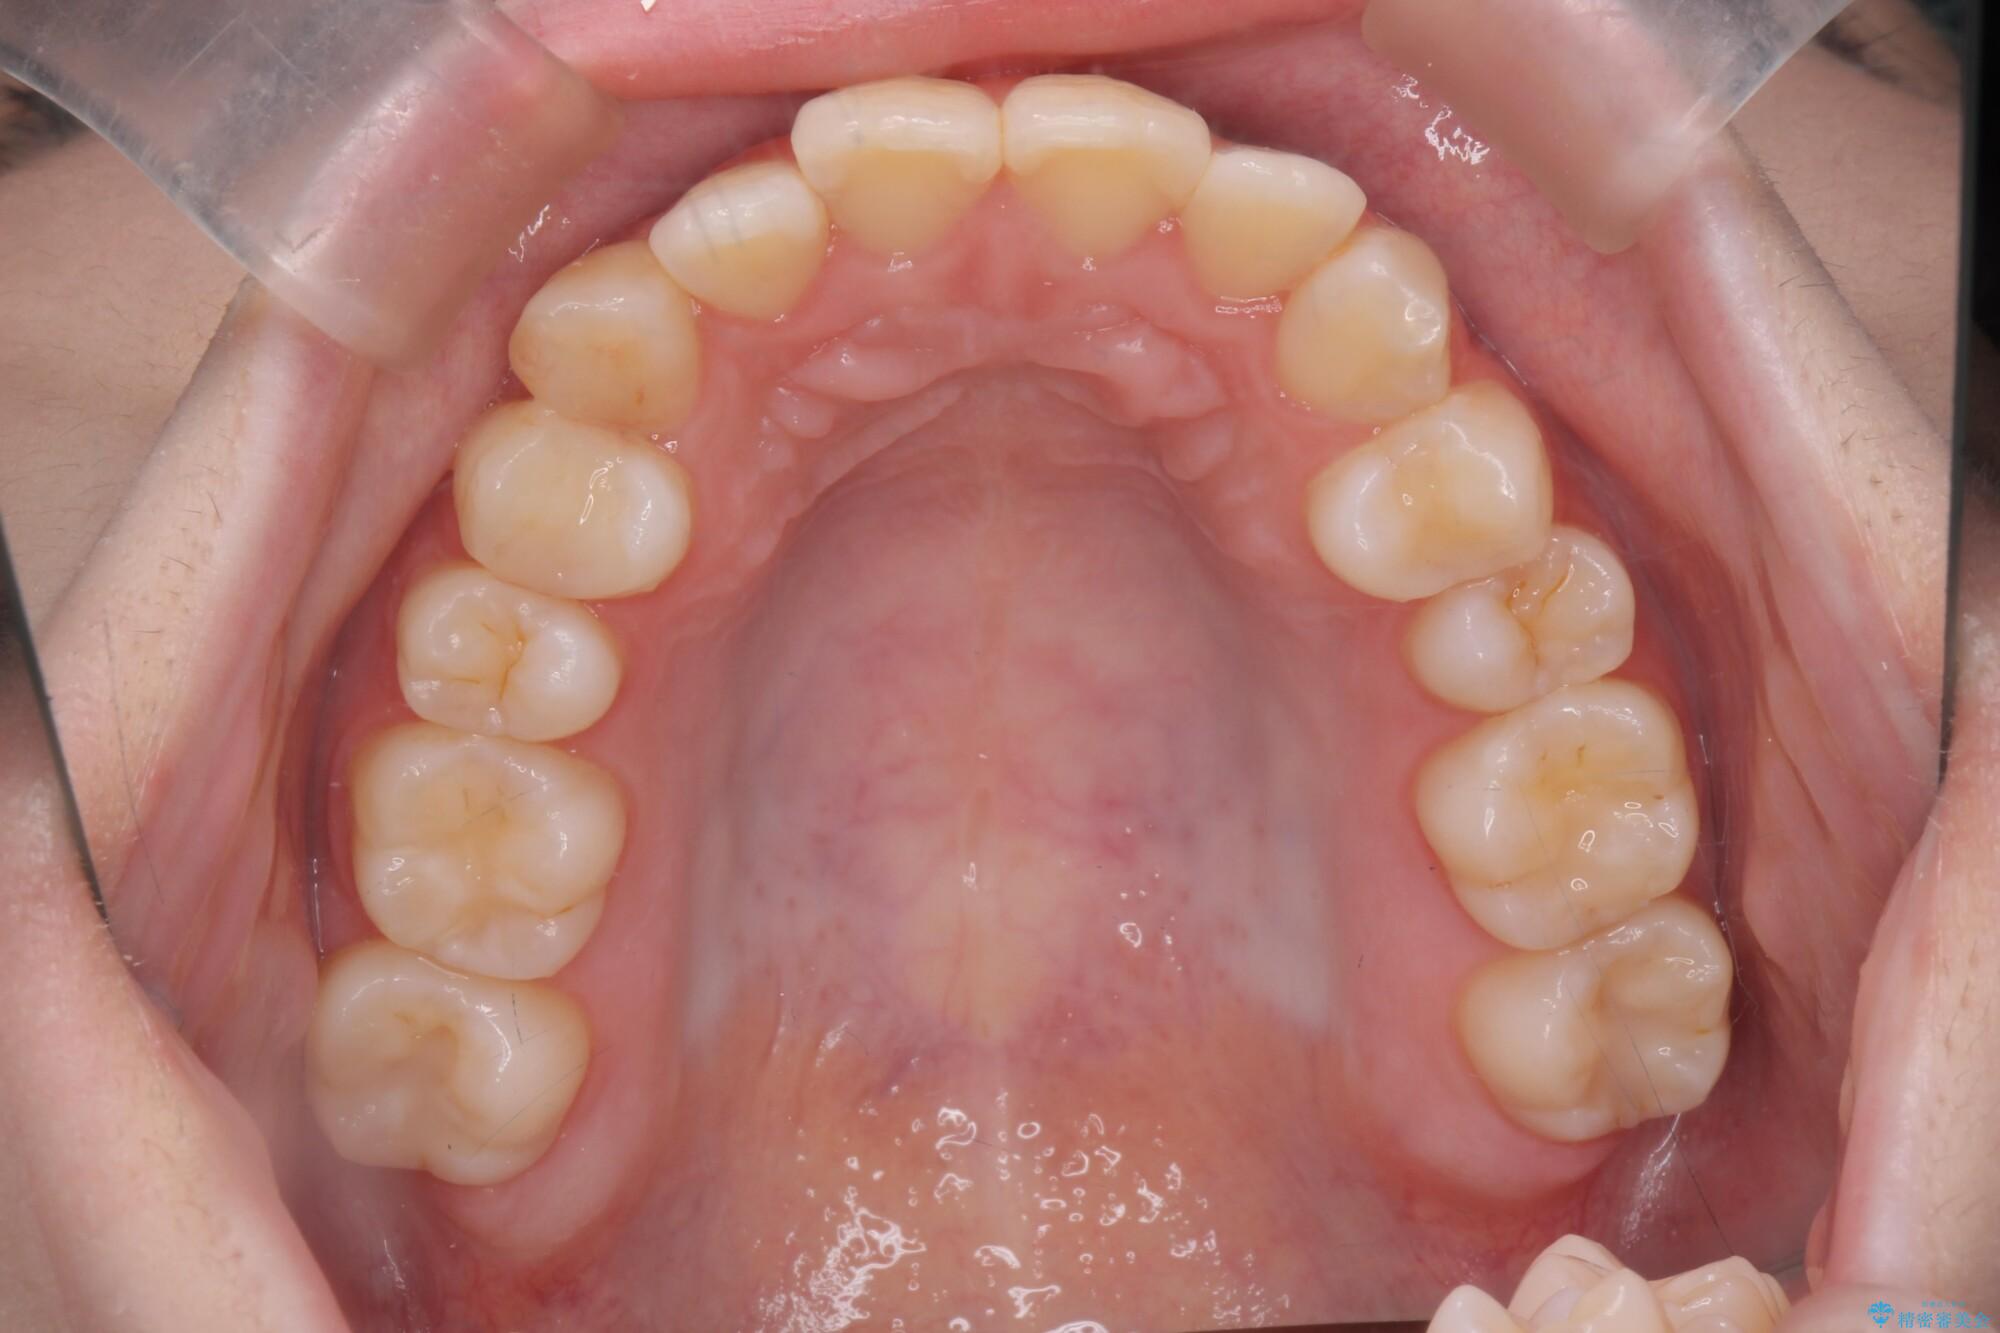

治療前

奥歯のガタつきをマウスピース矯正で改善 治療前画像 奥歯のガタつきをマウスピース矯正で改善 治療前画像 奥歯のガタつきをマウスピース矯正で改善 治療前画像